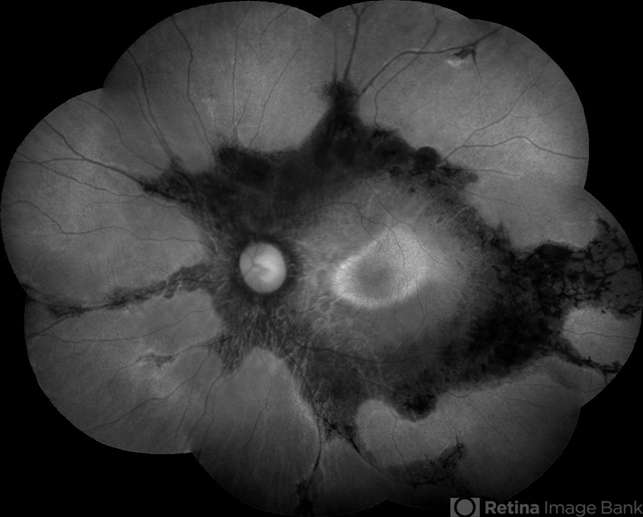

- Female patient, 32-years-old, Asian, appeared at the clinic with a history of glaucoma. 20/20 visual acuity in both eyes. Examination of color photography, pigmentary changes were observed following the vascular arcades only in the left eye. Suggestive of paravenous degeneration.